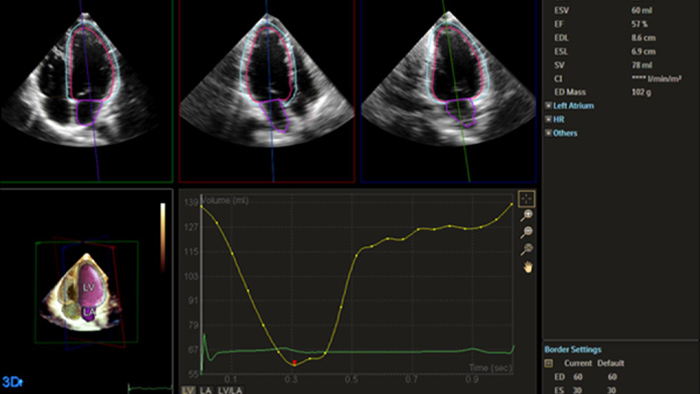

Quantification through Dynamic HeartModel.

Echo is often the first cardiac imaging test that’s performed for patients with suspected heart failure. An echocardiogram gives us a wealth of information on cardiac structure and function using both 2D and 3D tools. Echocardiography can help us understand the etiology of heart failure in many situations. I routinely use information derived from both 2D and 3D analysis and strain to better understand my patients. AutoStrain, Dynamic HeartModel and Auto RV are invaluable tools that are used both in the diagnosis and surveillance of patients with heart failure.”

Robust and reproducible imaging tools are important to diagnose and monitor disease progression in heart failure. Current guidelines support the use of advanced echocardiography tools such as longitudinal strain and 3D assessment of LV and RV volumes and function.